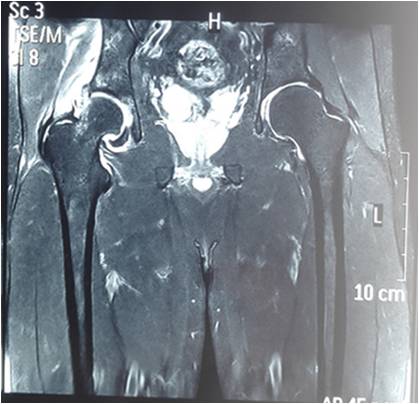

髋关节镜手术